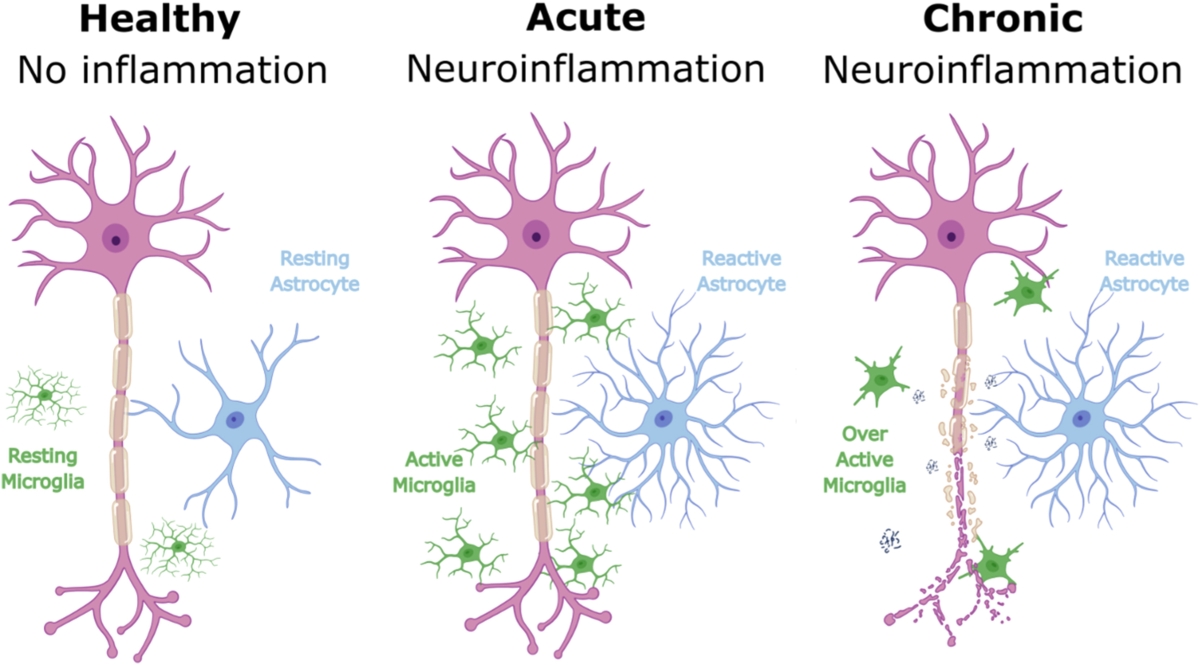

The authors interpret these findings as evidence that acute depressive symptoms and long standing depression history may reflect distinct biological processes. Elevated extracellular water markers may indicate chronic inflammatory states, while changes in microstructural markers may reflect more dynamic or acute inflammatory responses.

Feature Image – Cellular changes in response to varying degrees of inflammation. The figure illustrates the progression of neuroinflammation from a healthy state to acute and chronic inflammation